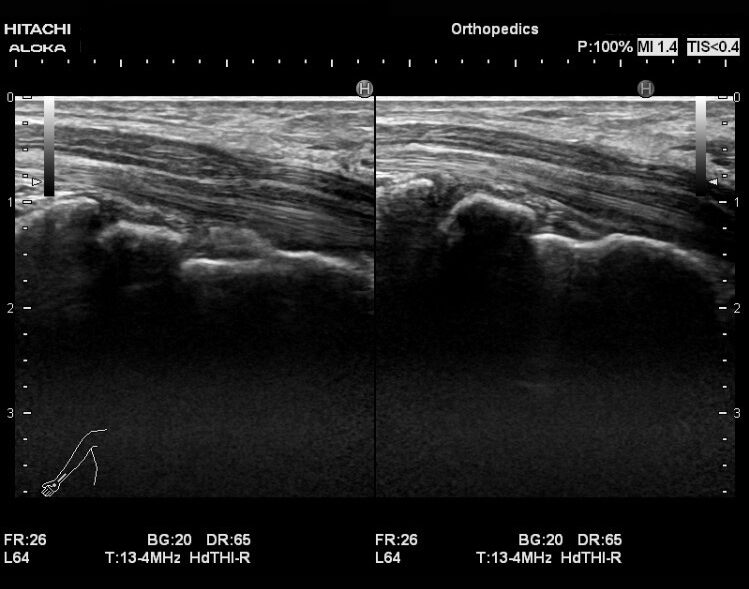

他の手や手首の繰り返しの動きと同様に、スマートフォンを長時間保持すると、正中神経への圧力が高まる可能性があります。

18歳以上の個人を対象とした2021年の研究では、1日2時間以上のスマートフォンの使用が手根管症候群の発症と関連していることが判明した。